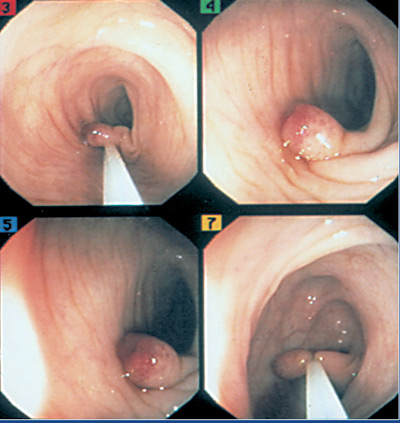

ΙV. Είναι αναμφισβήτητη η διαγνωστική και επεμβατική αξία της οισοφαγοσκόπησης.

Επιπλέον, η οισοφαγοσκόπηση αποκαλύπτει "εικόνες" όπως διαβρωτικής

οισοφαγίτιδας ή εγκαύματος από κατάποση καυστικών ουσιών (εικόνα 5).

EIKONA 5. Διαγνωστική και

θεραπευτική ενδοσκόπηση. α. Διαβρωτική οισοφαγίτις. β. Διαστολή στενώσεως οισοφάγου

με μπαλόνια. γ. Έγχυση σκληρυντικής ουσίας σε κιρσούς.